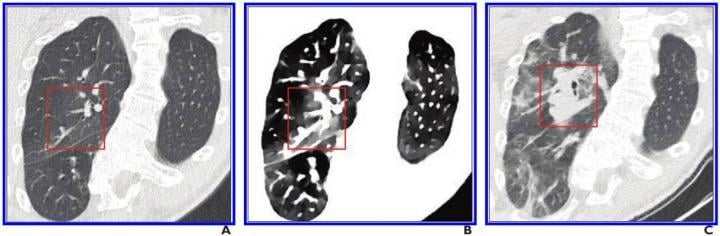

This photo gallery shows the variety of radiological presentations of COVID-19 (SARS-CoV-2) in medical imaging, including computed tomography (CT), radiograph X-rays, ultrasound, echocardiograms and magnetic resonance imaging (MRI). The radiology images show examples of typical COVID pneumonia in the lungs and the numerous complications the virus causes in the body in multiple organs, including the brain, kidneys, heart, abdomen and vascular system.

Ultrasound, especially hand-held ultrasound imaging devices, have become a primary imaging modality for novel coronavirus because of the ease to bag the device and sterilize it after use. CT and mobile X-ray systems are also used as front-line imaging systems for COVID-positive or suspected COVID patients.